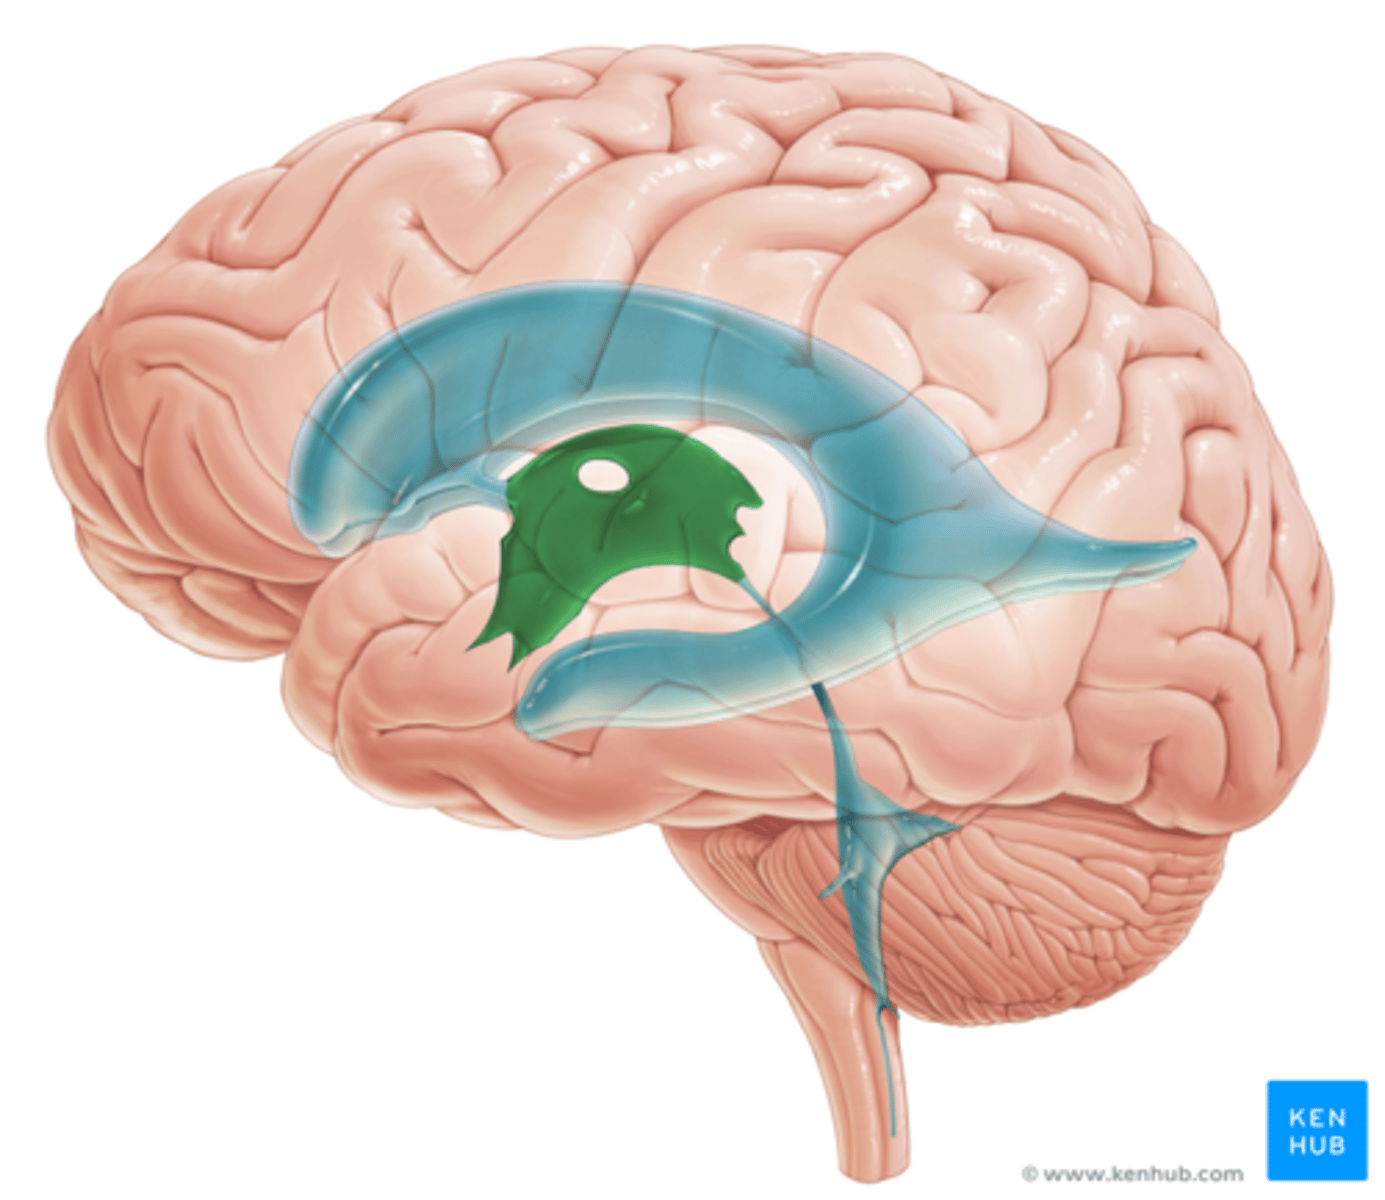

right and left lateral ventricles

third ventricle

fourth ventricle

cerebral aqueduct (mesencephalic aqueduct)

interventricular foramen